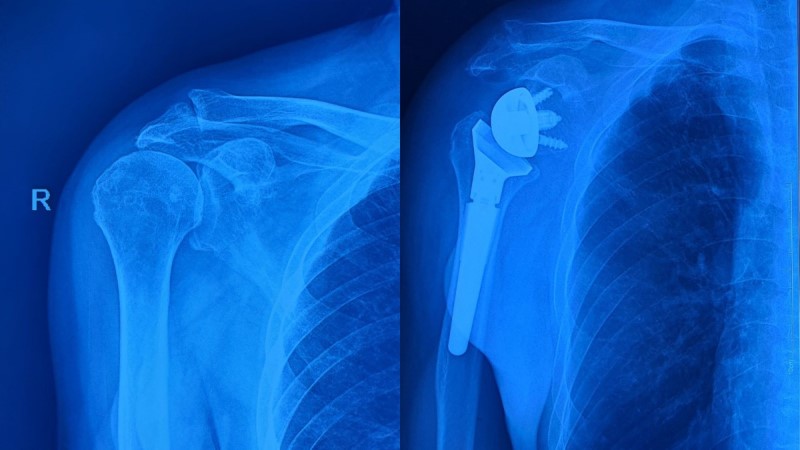

Khớp vai phải của bệnh nhân trước và sau phẫu thuật

Bệnh nhân T.P.V, 73 tuổi, ở Thành phố Huế, nhập viện trong

tình trạng rách lớn gân cơ chóp xoay và thoái hóa khớp vai phải mức độ nặng. Do

gân chóp xoay rách lớn tụt sâu về phía ổ chảo xương bả vai kèm theo tình trạng

thoái hóa gân nhiều nên việc khâu phục hồi là không khả thi.

Tiến hành hội chẩn, các bác sĩ chuyên khoa Chấn thương chỉnh hình – Bỏng – Y học thể thao đã chỉ định phẫu thuật thay khớp vai toàn phần đảo ngược - một kỹ thuật phức tạp và tiên tiến để điều trị cho bệnh nhân.